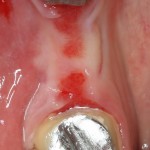

Клиническая картина в области удаленного зуба через полтора месяца:

Мечта имплантолога, не правда ли? Это я к тому, что не нужно ждать по полгода после удаления зуба — такой длительный срок ожидания приводит к сильной потере костной ткани. Не нужно превращаться в китайского пионера — самому себе создавать сложности, а потом героически их преодолевать.

Делаем разрез, скелетируем костную ткань. Вот еще один сюрприз:

Лунка зуба полностью регенерировала! Состояние костной ткани превосходное!

Это еще раз подтверждается, когда мы готовим лунку под имплантат:

Ну и, сам имплантат. Разумеется Friadent XiVE:

Еще раз напомню, что все полированные части импланта любой системы должны находиться выше уровня костной ткани. Как на фотографии.

При таких клинических условиях можно сразу приступить к формированию десны: